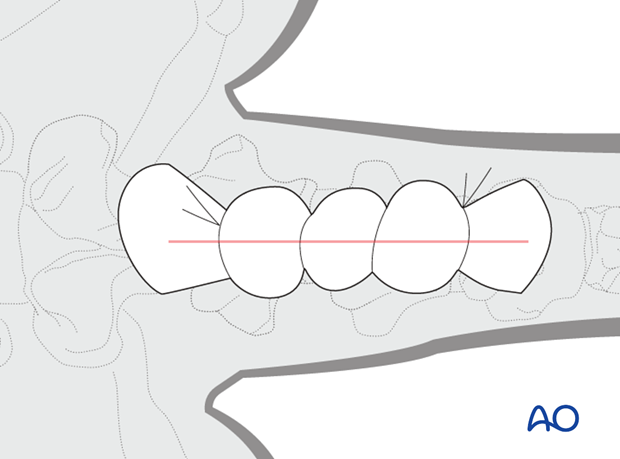

Lateral or oblique lateral radiographs confirm the presence of a vertebral fracture.